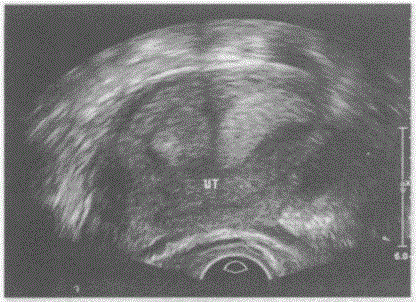

临床资料:女,25岁,自诉月经不规则。超声综合描述:横切面子宫底部平滑,横径增宽,内可见两个子宫内膜回声,中央有条样分隔,内膜汇合于子宫中下部呈"Y...

问题 临床资料:女,25岁,自诉月经不规则。 超声综合描述:横切面子宫底部平滑,横径增宽,内可见两个子宫内膜回声,中央有条样分隔,内膜汇合于子宫中下部呈"Y"形。 超声提示:

选项 A.完全性纵隔子宫 B.不完全性纵隔子宫 C.双子宫 D.双角子宫

答案 B